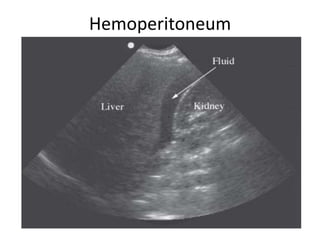

• Temuan Abnormal :

– Hemoperitoneum

• Regio anechoic antara hepar dan ginjal kanan atau pada

recessus subdiafragma

Hemoperitoneum

• Temuan Abnormal: – Hemoperitoneum • Regio anechoic antara hepar dan ginjal kanan atau pada recessus subdiafragma • Regio anechoic antara spleen dan ginjal kiri atau pada recessus subdiafragma – Hemotoraks • Regio anechoic diatas dari diafragma – Cedera organ padat (hepar / ginjal) – Hidronefrosis • Dilatasi sinus renalis dengan bayangan anechoic diantara sinus renal yang lebih terang